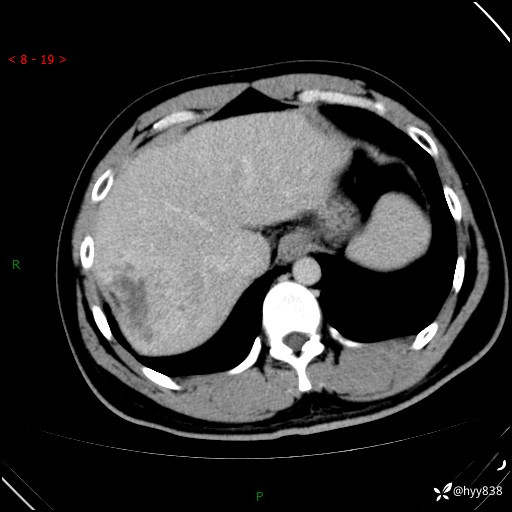

肝脏CT平扫

增强动脉期

静脉期

延迟期